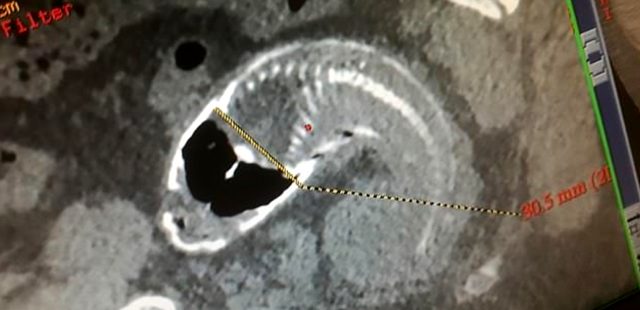

Ülkenin Guangdong eyaletinde, bir kişi karın ağrısı şikayetiyle hastaneye başvurdu. Kimliği açıklanmayan 30 yaşındaki kişi karın ağrısıyla Zhaoqing Hastanesi’ne gitti. Çekilen röntgende, adamın rektumunda (bağırsak) bir balığın olduğu görüldü. Hastanede gerçekleştirilen 5 saatlik operasyonla balık adamın vücudundan çıkarıldı. Yerel medya, söz konusu olayda adamın ‘yanlışlıkla’ balığın üzerine oturduğu bilgisine yer verdi.